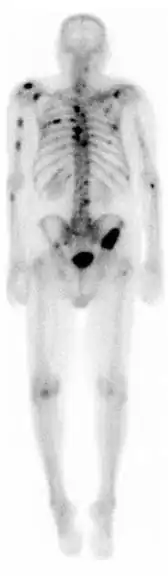

Knogleskintigrafi

Knogleskintigrafi er en nuklearmedicinsk metode til at vurdere sygdomme eller tilstande i skelettet. Ved at sprøjte et radioaktivt sporstof ind i en armvene og efter et stykke tid måle og visualisere optagelsen i skelettet og eventuelt bløddele ved hjælp af et gammakamera, kan sygdomsprocesser identificeres og vurderes. Knogleskintigrafi er velegnet til at påvise spredning af kræftsygdomme til knoglesystemet. Dette gælder blandt andet blærehalskirtelkræft og brystkræft. Knogleskintigrafi kan også anvendes til at påvise en bred vifte af led- og knoglesygdomme (inklusive infektioner i knogler og led) samt stofskiftesygdomme (bl. andet D-vitaminmangel og forhøjet stofskifte). Knogleskintigrafi kan også anvendes til at påvise betændelsestilstande som f.eks. Charcotfod.